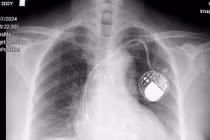

Bác sĩ đặt máy tạo nhịp không dây (điện cực) cho bệnh nhân - Ảnh BVCC

Máy tạo nhịp không dây có kích thước nhỏ gọn như viên thuốc hình con nhộng, bằng 1/10 máy tạo nhịp có dây, được cấy vào buồng tim của bệnh nhân thông qua ống thông, không cần dây dẫn.

Giáo sư Nhân cùng ê- kíp luồn ống thông qua tĩnh mạch đùi đến tâm thất phải. Dưới hướng dẫn của hình ảnh trên màn hình X-quang, các bác sĩ quan sát rõ đường đi của máy tạo nhịp đang nằm ở đầu ống thông trên màn hình X-quang, quá trình cấy máy diễn ra thuận lợi trong 45 phút.